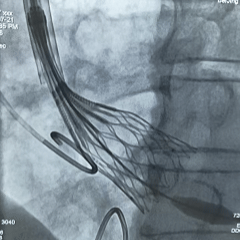

手术过程

左冠造影检查

20mm球囊扩张,无腰无漏,球囊轻微滑动

TF23瓣膜0位初始释放

瓣膜第一次展开造影评估,位置偏浅,回收调整

第二次释放造影评估

瓣膜深度可,展开良好,无瓣周漏

瓣膜解锁后造影评估

瓣膜深度合适形态良好,冠脉灌注良好,无瓣周漏

最终多角度观察瓣膜形态,瓣膜展开良好

超声测量流速1.5m/s,手术结束